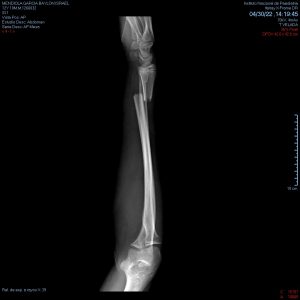

- Fracturas de miembros pélvicos

- Fracturas de fémur, tibia y peroné

Corrección de fracturas con mala consolidación

Hay algunos casos donde las fracturas pueden no sanar como es debido y generarse

deformidades angulares o torsionales las cuales afectan el movimiento correcto de las

articulaciones y pueden afectar la calidad de vida.